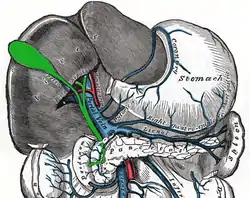

The cystohepatic triangle (or hepatobiliary triangle or Calot's triangle) is an anatomic space bordered by the cystic duct inferiorly, the common hepatic duct medially, and the inferior surface of the liver superiorly.

The hepatobiliary triangle is the area bounded by the:

- cystic duct inferiorly[1][2]

- common hepatic duct medially[1][2]

- inferior margin of the liver superiorly[1][2]

Another name used to refer to the hepatobiliary triangle is Calot's triangle, after Jean-François Calot.[6][7] Calot's original description of the triangle in 1891 included the cystic duct, the common hepatic duct, and the cystic artery (not the inferior border of the liver as is commonly believed).[4]